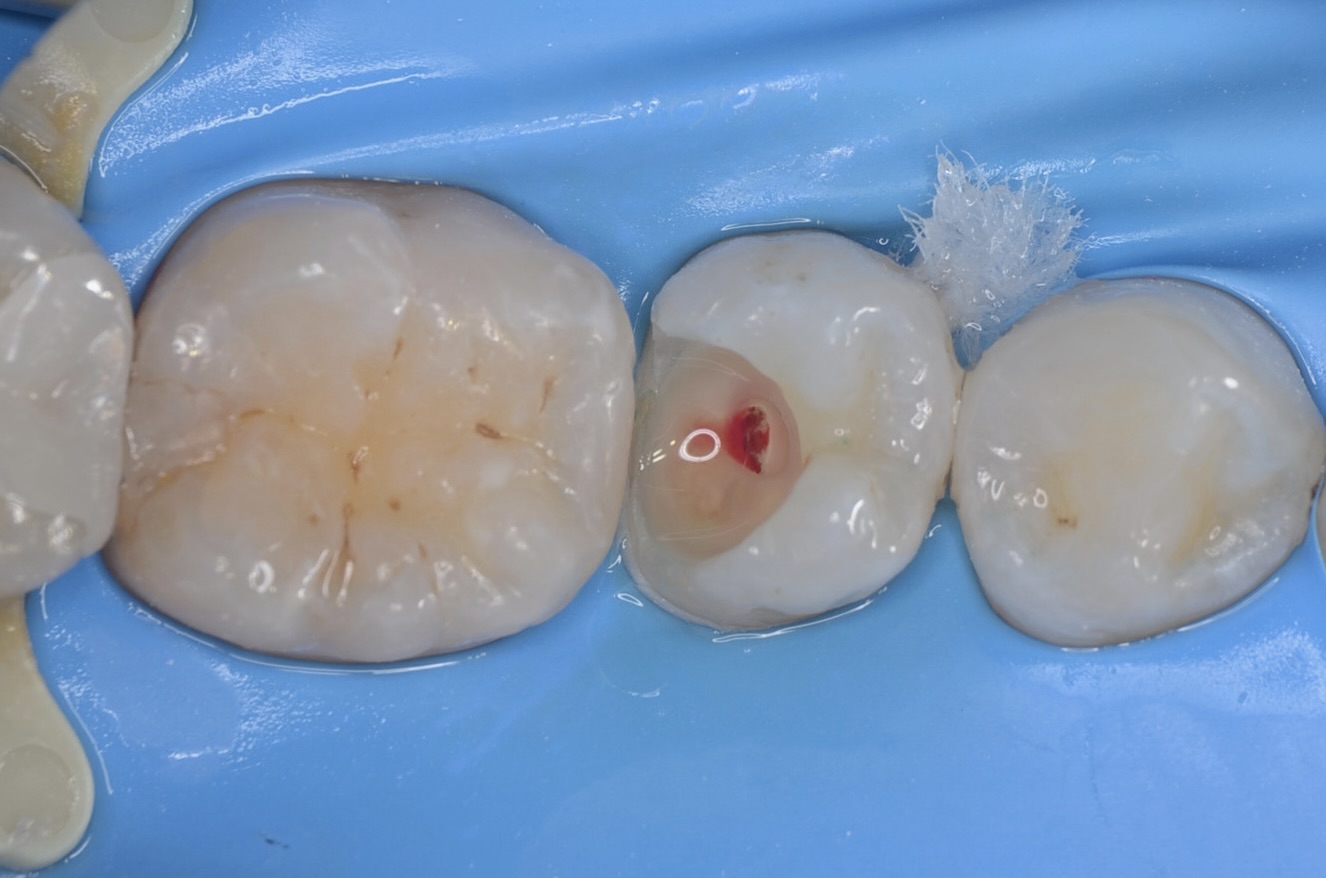

5番虫歯除去

青い齲蝕検知液で虫歯を染めて染まった部分を削ります。この工程を青く染まらなくなるまで歯にできるだけダメージがないように優しい力で丁寧に行います。この作業は時間がかかります。保険診療の短い時間で行うことは限界があります。 -

露髄

虫歯を完全に取り除くと出血してきました。 -